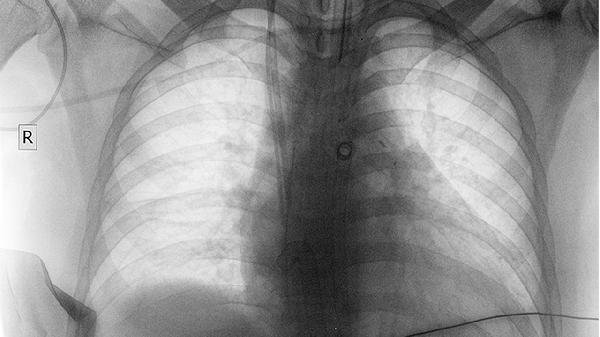

威麦宁胶囊含有的活性成分可能通过调节机体免疫功能,对肿瘤细胞增殖产生一定抑制作用。临床观察发现部分患者联合放化疗使用时,有助于稳定病灶。用药期间需定期复查影像学评估疗效。